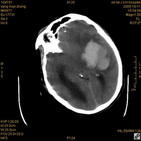

病人杨XX,男,青云街道办事处路踏泉村,住院号51666,CT号:104770。病人因“高血压脑出血”在新泰市人民医院住院治疗5天,治疗效果不佳转入我院,复查CT示左基底节血肿,病人昏迷状态,给予血肿清除术,术后2天复查CT,血肿完全清除,病人恢复好,治疗效果满意。附病人术前术后CT片资料如下。

术后46小时复查CT

术后46小时复查1 术后46小时复查2 术后46小时复查3 术后46小时复查4